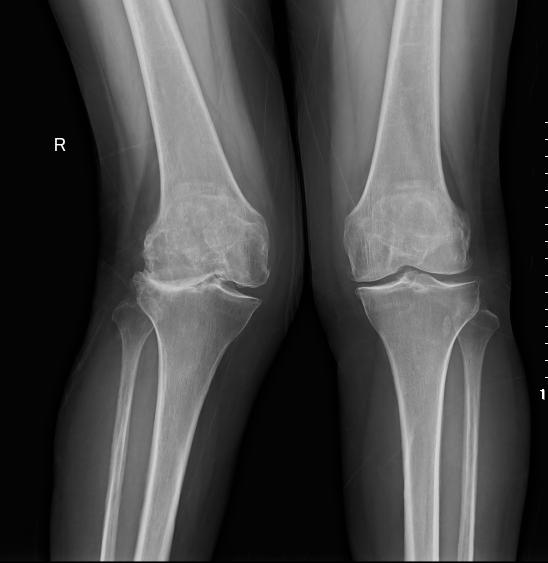

图3a 原发性单侧膝关节炎已至晚期(跛行步态,右膝屈曲外翻畸形,内侧间隙压痛)

图3b 原发性单侧膝关节炎已至晚期(跛行步态,右膝屈曲外翻畸形,内侧间隙压痛)